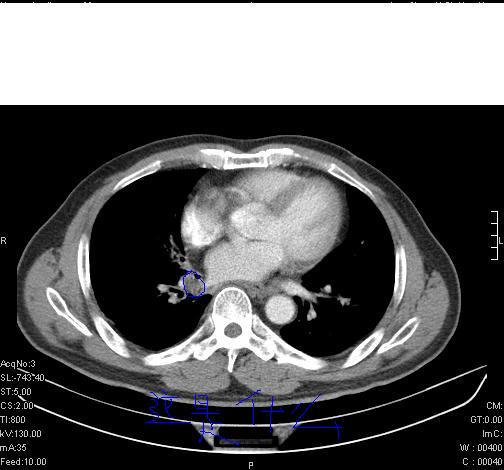

标题: CT6685:右肺阻塞性炎症,增强CT。

前几天,发了患者的平扫片,患者抗炎一周后增强扫描。右中叶病灶吸收明显,但下叶病灶未见明显吸收。右肺门可见结节影,看来凶多吉少

右肺下叶支气管管腔狭窄,管壁增厚,右下肺见斑片状高密度影,考虑右侧肺门中心肺癌伴阻塞性肺炎

第18幅,好像不能简单用炎症解释,前几天我发平扫时,90%人支持肺癌,现在好像大家更倾向于炎症了,我觉得还是不能排除肺癌。

右肺下叶支气管壁明显增厚,考虑癌症并阻塞性炎症、肺门淋巴结肿大

考虑右肺癌并阻塞性炎症、肺门淋巴结肿大

还是考虑右肺中央型肺癌可能性大

右肺下叶支气管壁不规则增厚,右肺下叶有斑片状影分布。考虑右肺中央型肺癌伴右肺下叶阻塞性改变。建议支纤镜检查。平扫比增强较好显示了病变情况。

右主支气管狭窄,管壁增厚。考虑右中心性肺ca伴阻塞性肺炎。

既然抗炎治疗有效,可继续治疗;右肺下叶支气管管腔狭窄,管壁增厚,右下肺见斑片状高密度影,右侧主支气管后见结节影(淋巴结?),肺癌不能排出。